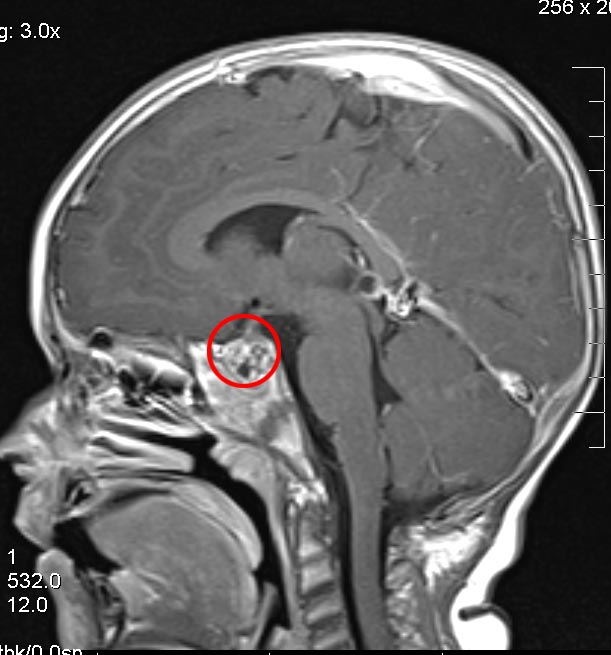

Eli's health is great (in many ways better than ever) and he seems to have completely recovered from the surgery. They seem to have gotten nearly all of the tumor. There is a little bit of tumor tissue left in the sella as shown in the picture below from his MRI on July 7. We are hopeful that this mass will remain stable for as long as possible to avoid radiation or another surgery until he is older. He'll have another MRI in October and hopefully everything will look exactly the same.